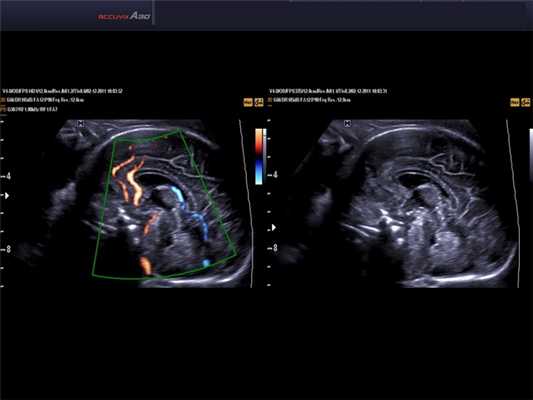

[EN] Эхограмма №566: Головной мозг плода в режиме DPDI (двунаправленный энергетический допплер), THI (тканевая гармоника) и DMR.

Изображение получено с помощью УЗ сканера Accuvix-A30 (снят с производства).

Результаты исследования: размеры плода пропорциональные, соответствуют менструальному сроку беременности. При эхокардиографии особенностей строения сердца у плода не выявлено. При оценке органов мочевыделительной системы обнаружено следующее: правая почка плода нормальных размеров и структуры. Левая почка увеличена до размеров 53х38х46 мм при 95-м процентиле нормативных для срока значений 43х24х23 мм [4] (рис. 1). В структуре почки, преимущественно в верхнем и среднем сегментах, определяется округлое образование без четких контуров, средней эхогенности, приблизительные размеры его 50х35х35 мм. При цветовом допплеровском картировании в образовании визуализируется обширная сосудистая сеть. При допплерометрии индексы сосудистой резистентности (рис. 2) в разных участках образования варьируют в широких пределах (от 0,49 до 0,77).

Рис. 2. Режим цветового допплеровского картирования. Хорошо видны различия в характере васкуляризации нормальной почки и контрлатеральной пораженной почки.